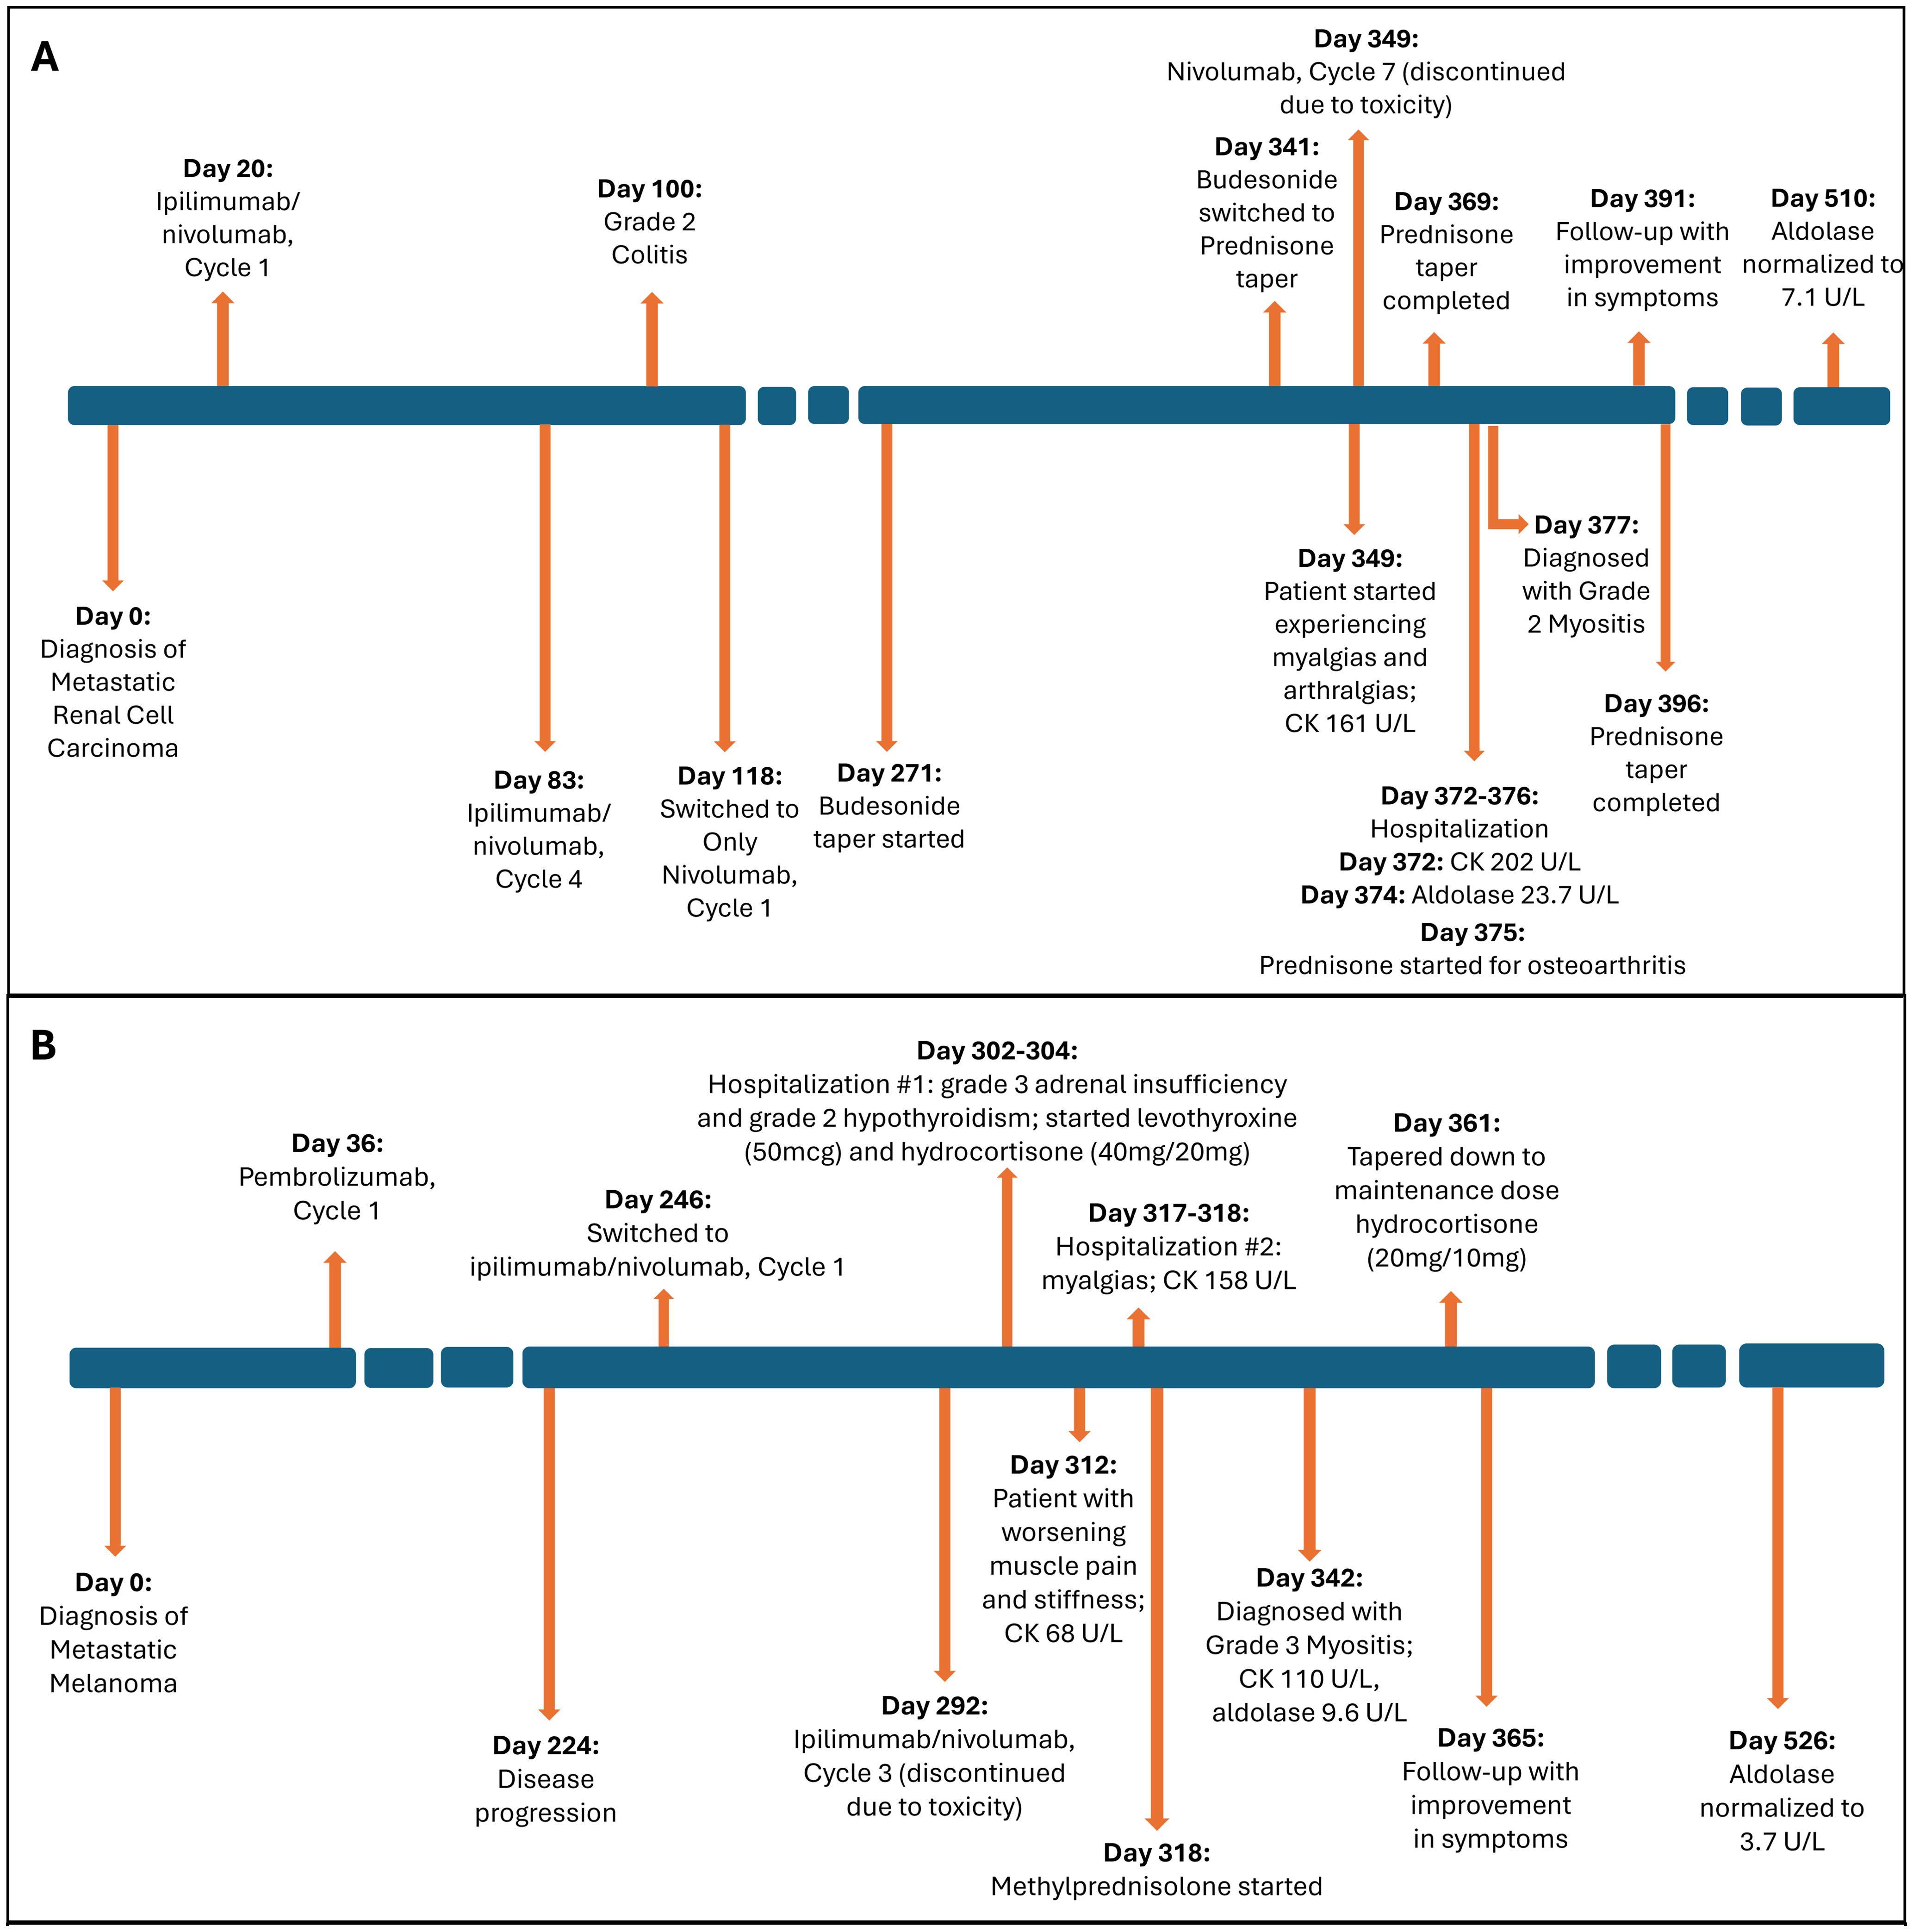

- 1Department of Internal Medicine, College of Medicine, The Ohio State University, Columbus, OH, United States

- 2Department of Internal Medicine Division of Medical Oncology, Department of Internal Medicine, James Comprehensive Cancer Center, The Ohio State University, Columbus, OH, United States

- 3Department of Internal Medicine Division of Rheumatology and Immunology, The Ohio State University, Columbus, OH, United States

Immune checkpoint inhibitors (ICIs) have been revolutionary in the field of cancer therapeutics. Myositis is a known rheumatic immunotherapy related adverse event with a fatality rate of 26.8% when associated with myasthenia gravis and 51.3% when associated with myocarditis. Typically, creatine kinase (CK) is elevated in ICI-myositis, thus normal CK levels in such cases may delay diagnosis and treatments in such patients. We report 2 cases of patients diagnosed with ICI-myositis after ipilimumab/nivolumab treatment for metastatic renal cell carcinoma and metastatic melanoma. Their lab studies showed normal CK values but elevated aldolase, which led to the ICI-myositis diagnosis and steroid treatment. Early recognition and treatment with steroids led to symptom improvement. These 2 cases highlight an atypical presentation of ICI-myositis with normal CK but elevated aldolase levels, suggesting aldolase may be a sensitive parameter in diagnosing ICI-myositis.

Immune checkpoint inhibitors (ICIs) have been revolutionary in cancer therapeutics. They block certain immune regulatory checkpoint proteins, allowing for the body’s immune system to target and attack the cancer cells. However, these powerful agents are also known to cause various adverse effects on organs, known as immune-related adverse events (irAEs). Myositis is a known rheumatic irAE. Although relatively rare, accounting for approximately 0.38-0.6% of irAEs, it is one of the most severe forms of rheumatic irAEs with a case fatality rate of 26.8% when associated with myasthenia gravis and 51.3% when associated with myocarditis (1). Studies have shown a significantly increased risk of developing myositis in patients treated with ICIs compared to those not treated with ICIs (2).

There is limited data on ICI-associated myositis in terms of clinical presentation and laboratory parameters required to establish a diagnosis. Typically, in ICI-myositis, creatine kinase (CK) is elevated (2). Here, we present 2 cases of ICI-myositis with a normal CK and elevated aldolase levels, both of which responded well to steroids.

2 Case presentations

2.1 Case 1

We report a case of a 72-year-old male with a history of paroxysmal atrial fibrillation who presented with cough and dyspnea for 2 months. His computed tomography (CT) chest scan revealed multiple solid noncalcified bilateral pulmonary nodules, and an indeterminate 6.5-cm left renal mass with multiple heterogenous left perinephric nodules concerning for regional spread of disease and associated left urothelial thickening. A lung biopsy revealed metastatic renal cell carcinoma, clear cell type.

He was started on ipilimumab (91mg)/nivolumab (274mg). He completed 4 cycles (9 weeks) with partial response. He developed grade 2 colitis (per Common Terminology Criteria for Adverse Events [CTCAE], version 5) (3) after the 4 treatment cycles and was switched to nivolumab alone (480 mg). He was treated with a prolonged budesonide taper (entailing 9 mg daily for 2 weeks, then 6 mg daily for 2 weeks, then alternation between 6 mg and 3 mg daily for 2 weeks, then 3 mg daily for 2 weeks, then alternation between 3 mg and 0 mg daily for 2 weeks). This was followed by a prednisone taper (entailing 5 mg daily for 2 weeks, then 2.5 mg daily for 2 weeks). He continued immunotherapy until cycle 7 (33 weeks) after which he developed symptoms of diffuse myalgias, joint stiffness, and fatigue. The CK level obtained at that time was normal (161 U/L). He became unable to perform his activities of daily living requiring hospital admission within that month. This was approximately 5 days after completing the prednisone taper and 8 months after starting nivolumab alone. His labs were notable for white blood cell count (WBC) (15.9 K/uL), C-reactive protein (26 mg/L), elevated transaminases (aspartate aminotransferase [AST], 99 U/L and alanine aminotransferase [ALT], 102 U/L), and normal CK (202 U/L), all of which were collected around 101 days from when budesonide was started. The autoimmune workup including rheumatoid arthritis (RA), and systemic lupus erythematosus (SLE) was negative (Table 1). Viral causes tested included hepatitis C which was negative. A right wrist x-ray was obtained for further evaluation of severe wrist pain and stiffness which showed diffuse soft tissue swelling (Figure 1). Initially, symptoms were thought to be due to osteoarthritis. He was discharged with prednisone 20mg daily for 7 days, which was tapered to 5mg daily over 3 weeks. The aldolase level (which was collected approximately 103 days from when the budesonide course was started) was found to be elevated at 23.7 U/L (reference range: < 7.7 U/L). He was diagnosed with grade 2 myositis (Figure 2) (3). Grade was determined according to the CTCAE v.5 which was based on severity of symptoms and interference with activities of daily living (3). Muscle MRIs and electromyograms (EMG) were not performed. A muscle biopsy was not completed since the patient already received steroid treatment with budesonide. Given improvement in symptoms, he was continued on the steroid regimen and tolerated it well. At his 2-week follow-up visit, his myalgia had improved. His aldolase level gradually declined back to normal (7.1 U/L) over the following 5 months. Immunotherapy was discontinued given 2 irAEs. Staging scans that were obtained after discontinuing immunotherapy revealed partial response. The patient remains off treatment and on surveillance.

Figure 1. Right wrist x-rays. (A) DA and lateral filme of right wrist ob Im (B) Lateral film diffuse soft tissue inflammation.

Figure 2. Timeline of event. (A) Case 1. (B) Case 2. Figure illustrating timeline of major events including diagnosis, treatment, laboratory parameter for the 2 cases. CK, creatine kinase.

2.2 Case 2

We report a case of a 60-year-old male with no significant medical history who presented with left axillary mass with pain for about 1 week. A positron emission tomography-CT (PET-CT) scan revealed hypermetabolic activity in the left axillary mass. A biopsy revealed metastatic stage IV melanoma of unknown origin (SOX10 positive, Melan-A positive, S100 protein positive) with a BRAF p.V600E mutation. A brain magnetic resonance imaging (MRI) scan was completed for staging, which revealed no brain metastases (Figure 3).

Figure 3. Brain MRI w/wo contrast pre- and post-immunotheraphy. (A) pre-immunotheraphy initiation; (B) post-immunotheraphy initiation.

He began pembrolizumab (400 mg) as neoadjuvant therapy and completed 5 cycles (24 weeks), with suboptimal response. The treatment was changed to ipilimumab (225 mg)/nivolumab (72.9 mg) as there was disease progression with metastasis to lymph nodes with extracapsular extension. After completing 3 cycles (7 weeks), he developed symptoms of diffuse muscle pain and fatigue requiring hospitalization. He was found to have abnormal blood chemistries including hyponatremia (sodium [Na], 118 mmol/L), hypocortisolism (cortisol, 1.01 mcg/dL), and hypothyroidism (thyroid-stimulating hormone [TSH], 0.274 uIU/mL, free thyroxine [T4], 0.66 ng/dL, free triiodothyronine [T3], 2.2 pg/mL). A brain MRI revealed an enlarged pituitary gland compared to his prior scan (from 9 months earlier), and with a new hypo-enhancing pituitary lesion (Figure 3). These findings were consistent with hypophysitis resulting in grade 3 adrenal insufficiency and grade 2 hypothyroidism (3). At this time, his myalgias were attributed to this endocrinopathy, and he was started on hydrocortisone (40 mg in morning/20 mg in evening) which was tapered to a maintenance dose (20 mg in morning/10 mg in evening) and levothyroxine (50 mcg).

At his 1-week follow-up visit, while on the maintenance dose, his muscle pain and stiffness worsened. Unsure if his endocrinopathy was worsening or if he was not receiving the correct treatment, further blood work was completed. He had a normal CK level (68 U/L), so myositis was ruled out. Despite myositis being ruled out, he was hospitalized again for persistent symptoms. This was approximately 10 weeks after starting ipilimumab/nivolumab. At that time, his labs were notable for a normal CK (158 U/L) and elevated transaminases (AST, 49 U/L and ALT, 91 U/L). His autoimmune workup including RA, SLE was negative otherwise (Table 1). Hepatitis C was negative. He was ultimately discharged with methylprednisolone (1mg/kg) for debilitating pain attributed to an unknown autoimmune/inflammatory syndrome from immunotherapy treatment. This was tapered over the next 6 weeks back to his prior maintenance dose. During his admission, a muscle biopsy was not completed as he had already received steroid treatment for his hypophysitis. Additionally, muscle MRIs and EMGs were not performed. He was seen at a follow-up visit 3 weeks after discharge. His aldolase level was checked (which was approximately 24 days from when methylprednisolone was started) and was elevated (9.6 U/L). His CK level remained normal (110 U/L). He was diagnosed with grade 3 myositis (Figure 2) (3). He continued the methylprednisolone taper since it was well-tolerated and resumed his maintenance hydrocortisone dose around 3 weeks later. At follow-up visit that week, he had improvement in myalgias. His aldolase level normalized to 3.7 U/L over the following 6 months. Immunotherapy was discontinued given 2 irAEs requiring hospitalization. He remains on surveillance with no evidence of active disease on staging scans.

3 Discussion

These 2 cases highlight an atypical presentation of immunotherapy-related myositis with normal CK levels but elevated aldolase levels that responded to steroid treatment.

ICI-myositis typically occurs with CK elevation, which was not the case in this report; it is important to note that the aldolase level was elevated, suggesting that this may be a sensitive laboratory marker in the diagnosis of ICI-myositis.

Aldolase elevation suggests damage of early regenerating muscle cells, which is not well understood; however, there are a few descriptive cases in rheumatology (4). In a study, aldolase A mRNA that was isolated from cultured human myoblasts and protein expression was highest in early differentiating myoblasts and remained elevated throughout differentiation, in contrast to CK mRNA and protein levels which remained low initially but increased as differentiation progressed (4). There have been several clinical studies showing a similar pattern of normal CK and elevated aldolase levels. In one study of 66 patients with dermatomyositis, 17 (26%) of them had normal CK with elevated aldolase (5). In another study, there were 12 patients with polymyositis confirmed on muscle biopsy, all of whom had a normal CK level with an elevated aldolase similar to our cases (6). There was another study of 34 patients with various myopathies including dermatomyositis, overlap myositis, and nonspecific myopathy. All of these patients were also found to have normal CK with elevated aldolase levels (7). This suggests that an elevated aldolase is a sensitive marker for many of these autoimmune myopathies and potentially ICI-myositis.

There have been a few studies exploring aldolase levels in patients with myopathy related to ICI use. In one retrospective study with 36 patients who either had ICI-myositis alone or with overlap manifestations including myocarditis and myasthenia gravis, 94% of the cohort had elevated CK levels and 26/27 patients tested had an elevated aldolase level (8). Two patients had a normal CK level, one of whom had elevated aldolase similar to our cases (8). Another retrospective study comparing patients with ICI myopathy to those with immune-mediated necrotizing myopathy (not exposed to immunotherapy) showed modest elevation in both aldolase and CK levels among the ICI myopathy group, but the elevation was far more prominent in the immune-mediated necrotizing myopathy group (9). Similar to our cases, 7/22 patients in the ICI myopathy group had normal CK levels, of which 2 had elevated aldolase levels (9). In contrast to our case series findings, there was another case series, of 2 patients who developed ICI-myositis following treatment with pembrolizumab who had both elevated CK and aldolase levels (10).

The variation in presentation of CK and aldolase levels seen in the literature further emphasizes the need for additional studies to better understand the diagnostic pattern for ICI-myositis. There is limited evidence on the diagnostic criteria for ICI-myositis. Presentation of ICI-myositis with a normal CK and elevated aldolase levels is rare. It may be that myositis is missed due to the diagnosis being dependent on an elevated CK level, which can lead to a delay in the diagnosis and treatment of such patients. This raises the question of whether aldolase should become part of the initial testing of patients for whom ICI-myositis is suspected.

The exact mechanism for an isolated elevated aldolase is unclear. A possible reason for this may include the extent of muscle fiber splitting and vacuolization of muscle fibers. Studies have shown patients with elevated CK have more frequent fibrillation potentials on EMG which correlate to presence of necrotic fibers, fiber splitting or vacuolization (7). Another explanation may be whether there is involvement of the perimysium. A study showed that 11/12 patients (92%) with isolated aldolase elevation had perimysial pathology (11). There needs to be further investigations exploring this to better understand the underlying mechanisms.

It is also important to note that both of our cases had prior steroid exposure for another ICI-related event, and so it is unclear whether the CK level was elevated before and normalized immediately upon starting steroids, or whether it was normal to begin with. Conversely, aldolase not only was elevated, but remained elevated for several months after the completion of steroids.

Studies have shown that patients in the acute setting of glucocorticoid-induced myopathy can have high aldolase levels with improvement within 3-4 weeks of discontinuing or reducing the steroid dose (12–14). This is typically seen at doses exceeding 60mg prednisolone daily (or equivalent) (12–14). Chronic steroid myopathy, however, is typically seen with steroid use for more than 4 weeks and in doses exceeding 10mg prednisolone daily (or equivalent) (12–14). In the setting of chronic steroid myopathy, aldolase levels have been shown to be typically normal (13). In the setting of inflammatory myopathies, or in our case of ICI-myositis, and prior steroid exposure, it becomes challenging to distinguish whether the aldolase elevation is due to the underlying disease or muscle damage related to the steroid. Studies have shown that EMG or muscle biopsy findings can aid in distinguishing between the two pathologies, however, these additional tests were not completed among our patients (13). Therefore, our study findings suggest that aldolase elevation may be a sensitive marker for ICI-myositis in the setting of prior steroid exposure. It is important to note, however, that for Case 1, he was started on steroids (with budesonide) over 10 weeks in advance from when aldolase was measured and tapered (Figure 2, box A). In this setting of chronic steroid use, we would expect to see normal aldolase levels. Additionally, after the completion of the steroid course (Case 1) or taper down to the maintenance dose (for adrenal insufficiency in Case 2), the aldolase level remained elevated for over 20 weeks which is atypical for steroid-induced myopathy, although further tests such as EMGs and muscle biopsies are needed to confirm.

ICI-myositis typically presents with progressive upper and lower extremity weakness within 2-3 months of ICI initiation, along with myalgias and fatigue. However, there can be additional clinical manifestations including ocular, cardiac, and even neurologic involvement. Studies report that oculo-bulbar symptoms can present in up to 25% of patients with ICI-myositis, an uncommon presentation seen with idiopathic inflammatory myopathies, unrelated to ICI use (15). These symptoms present as ptosis, ophthalmoplegia, dysphagia, and potentially dyspnea from diaphragm involvement. Additionally, studies report that myocarditis can concurrently occur in patients with ICI-myositis (2, 16, 17). In a study of 9,088 patients, around 36 (0.40%) patients had ICI-myositis, among which 14 (39%) patients had concurrent myocarditis (8). Neither of our two patients developed myocarditis and all cardiac work-up including EKG, troponins, and echocardiograms have been normal. Given these broad clinical manifestations and organ involvement that can be fatal if left untreated, it is even more important to recognize ICI-myositis so that appropriate therapy can be initiated.

The strengths of this case series include the fact that both patients at baseline had relatively few co-morbidities and took few medications. Medications they took were not commonly associated with myositis, thus limiting the confounding bias. One of the limitations of this case series is the lack of muscle biopsies to confirm the diagnosis of myositis; our diagnosis was based on clinical presentation and elevated aldolase levels. The inflammation seen on right wrist imaging for Case 1, however, did support the diagnosis. Additionally, both patients had prior steroid exposure for an irAE other than myopathy. This may have contributed to the normalization of CK levels at the time of ICI-myositis diagnosis and may also potentially confound the aldolase elevation seen. Further testing including EMG, muscle biopsies are needed to confirm.

4 Patient perspective

Both patients at follow up 2-3 weeks after diagnosis of ICI-myositis, and on steroid treatment, noted significant improvement in myalgias and ability to perform daily activities of living.

5 Conclusion

Myositis is a rare but potentially severe irAE. Early identification of the clinical symptoms and understanding the varied clinical manifestations is key in recognizing ICI-myositis and initiating appropriate treatment. This case series highlights that, along with clinical features, laboratory abnormalities, including aldolase elevation despite normal CK levels, may further aid in the early identification of ICI-myositis, especially in the setting of prior steroid exposure.